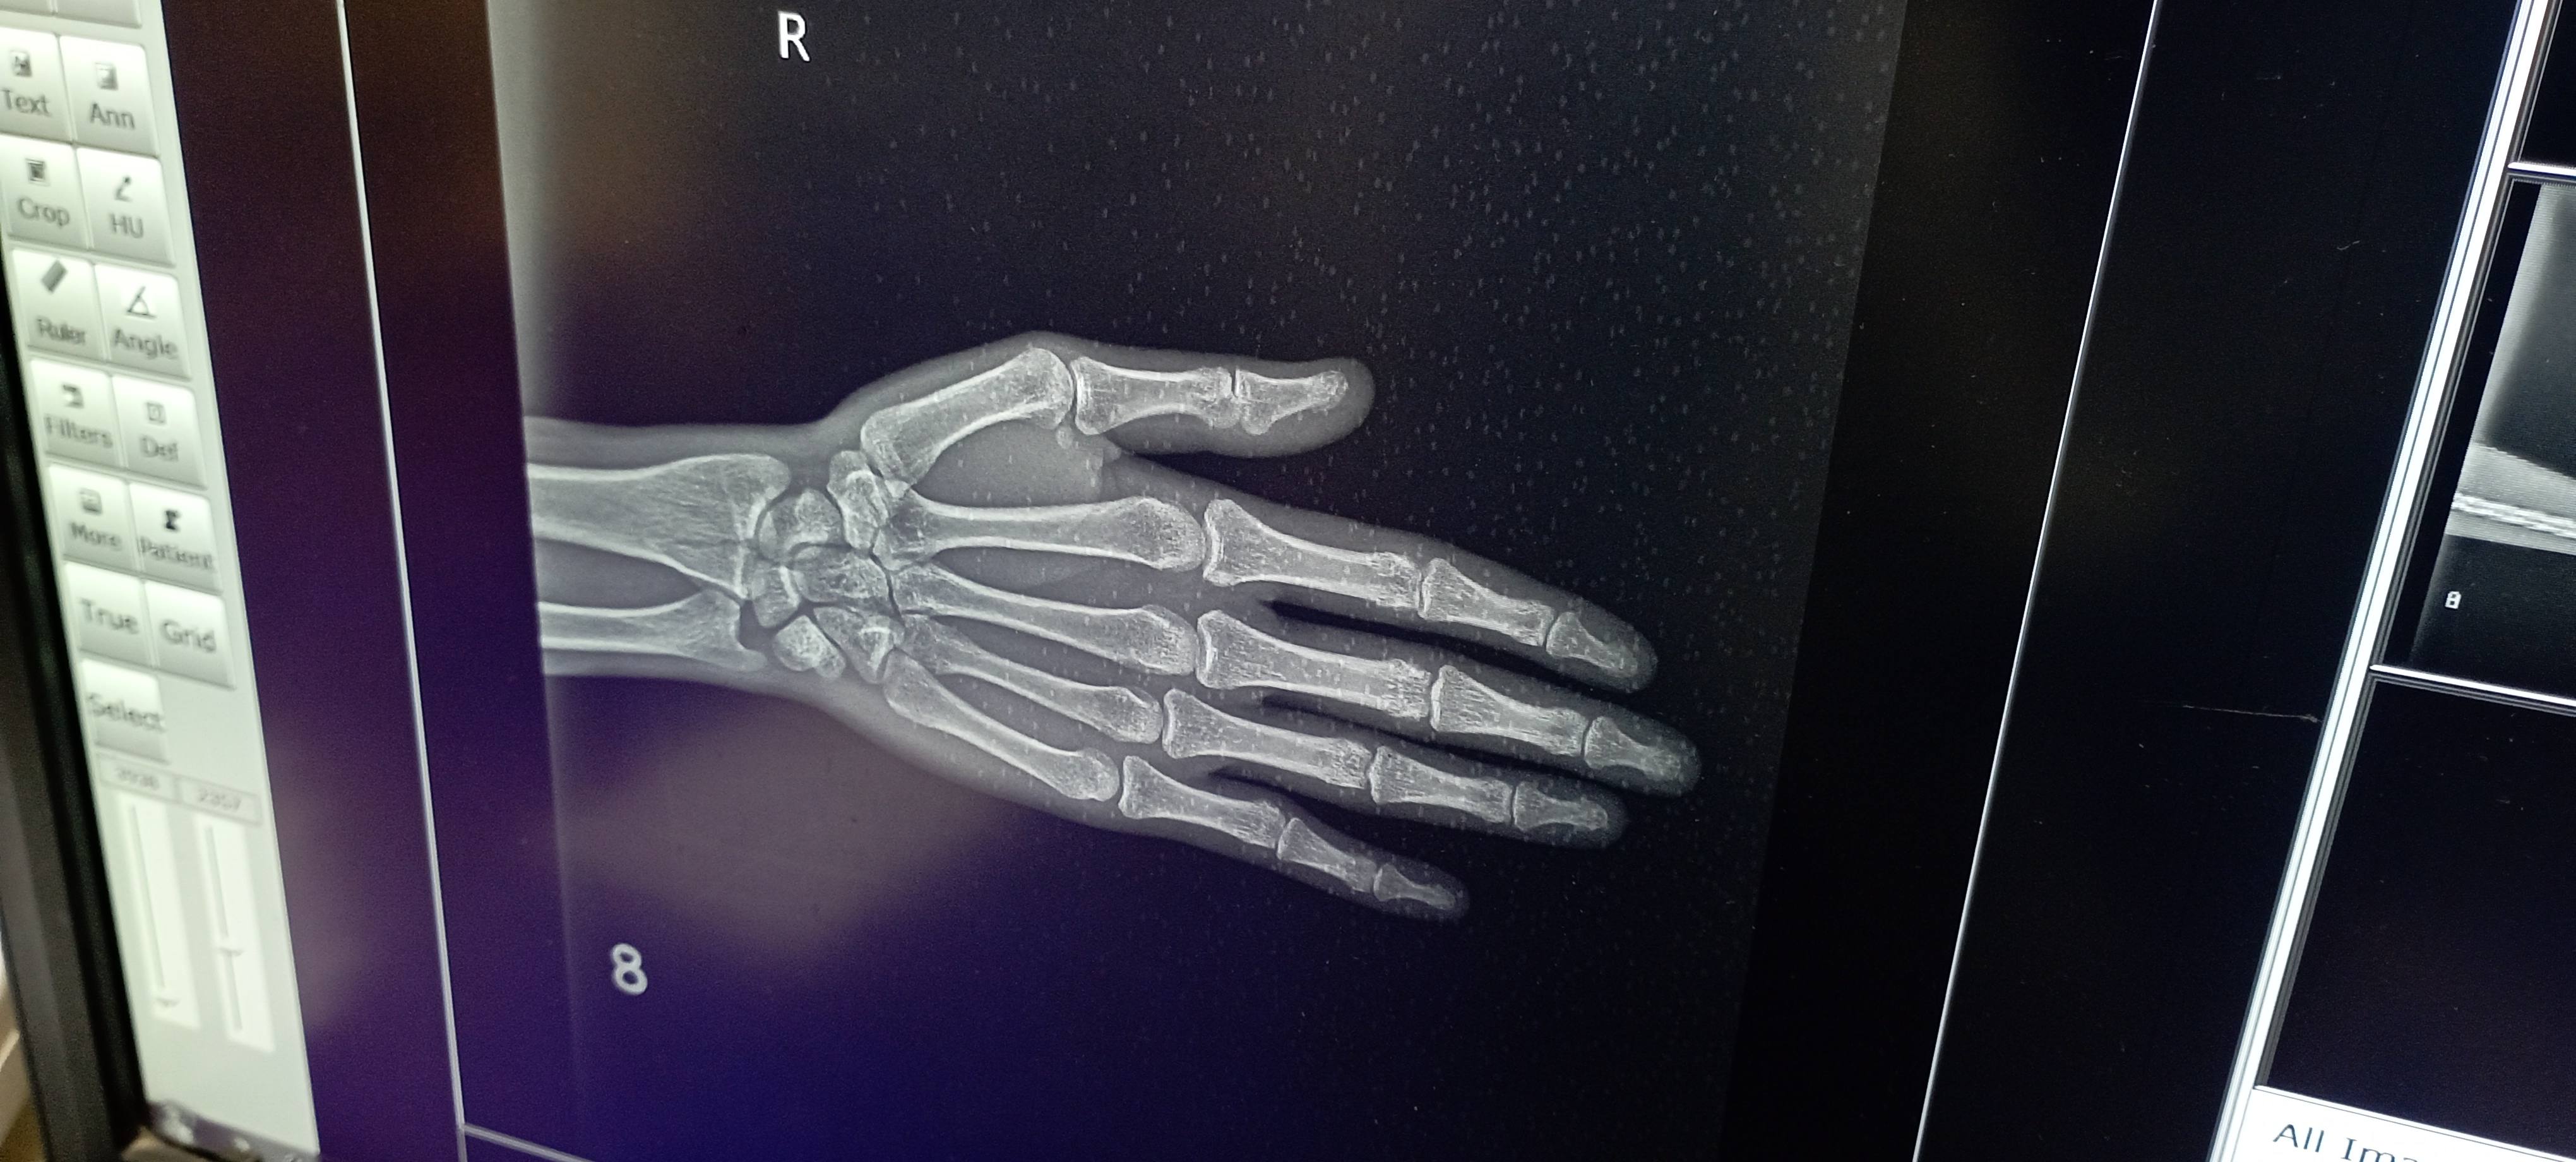

Sumit Yadav

Sir mai 26 sal ka hu,,, mujhe ek dr ne wrist me normal fracture btaya aur ek orthopedic surgeon Dr ne operation krna pdega bol rhe the lekin mere hat me moment Thik chl rhi lekin thoda hat mudne me problem aa rhi aur weight bhi dhire dhire utha pa rha hu ,,, pls sir kuch solution btayi kya kru ? ?,,, qki aage mera physical test bhi aa rha hai.